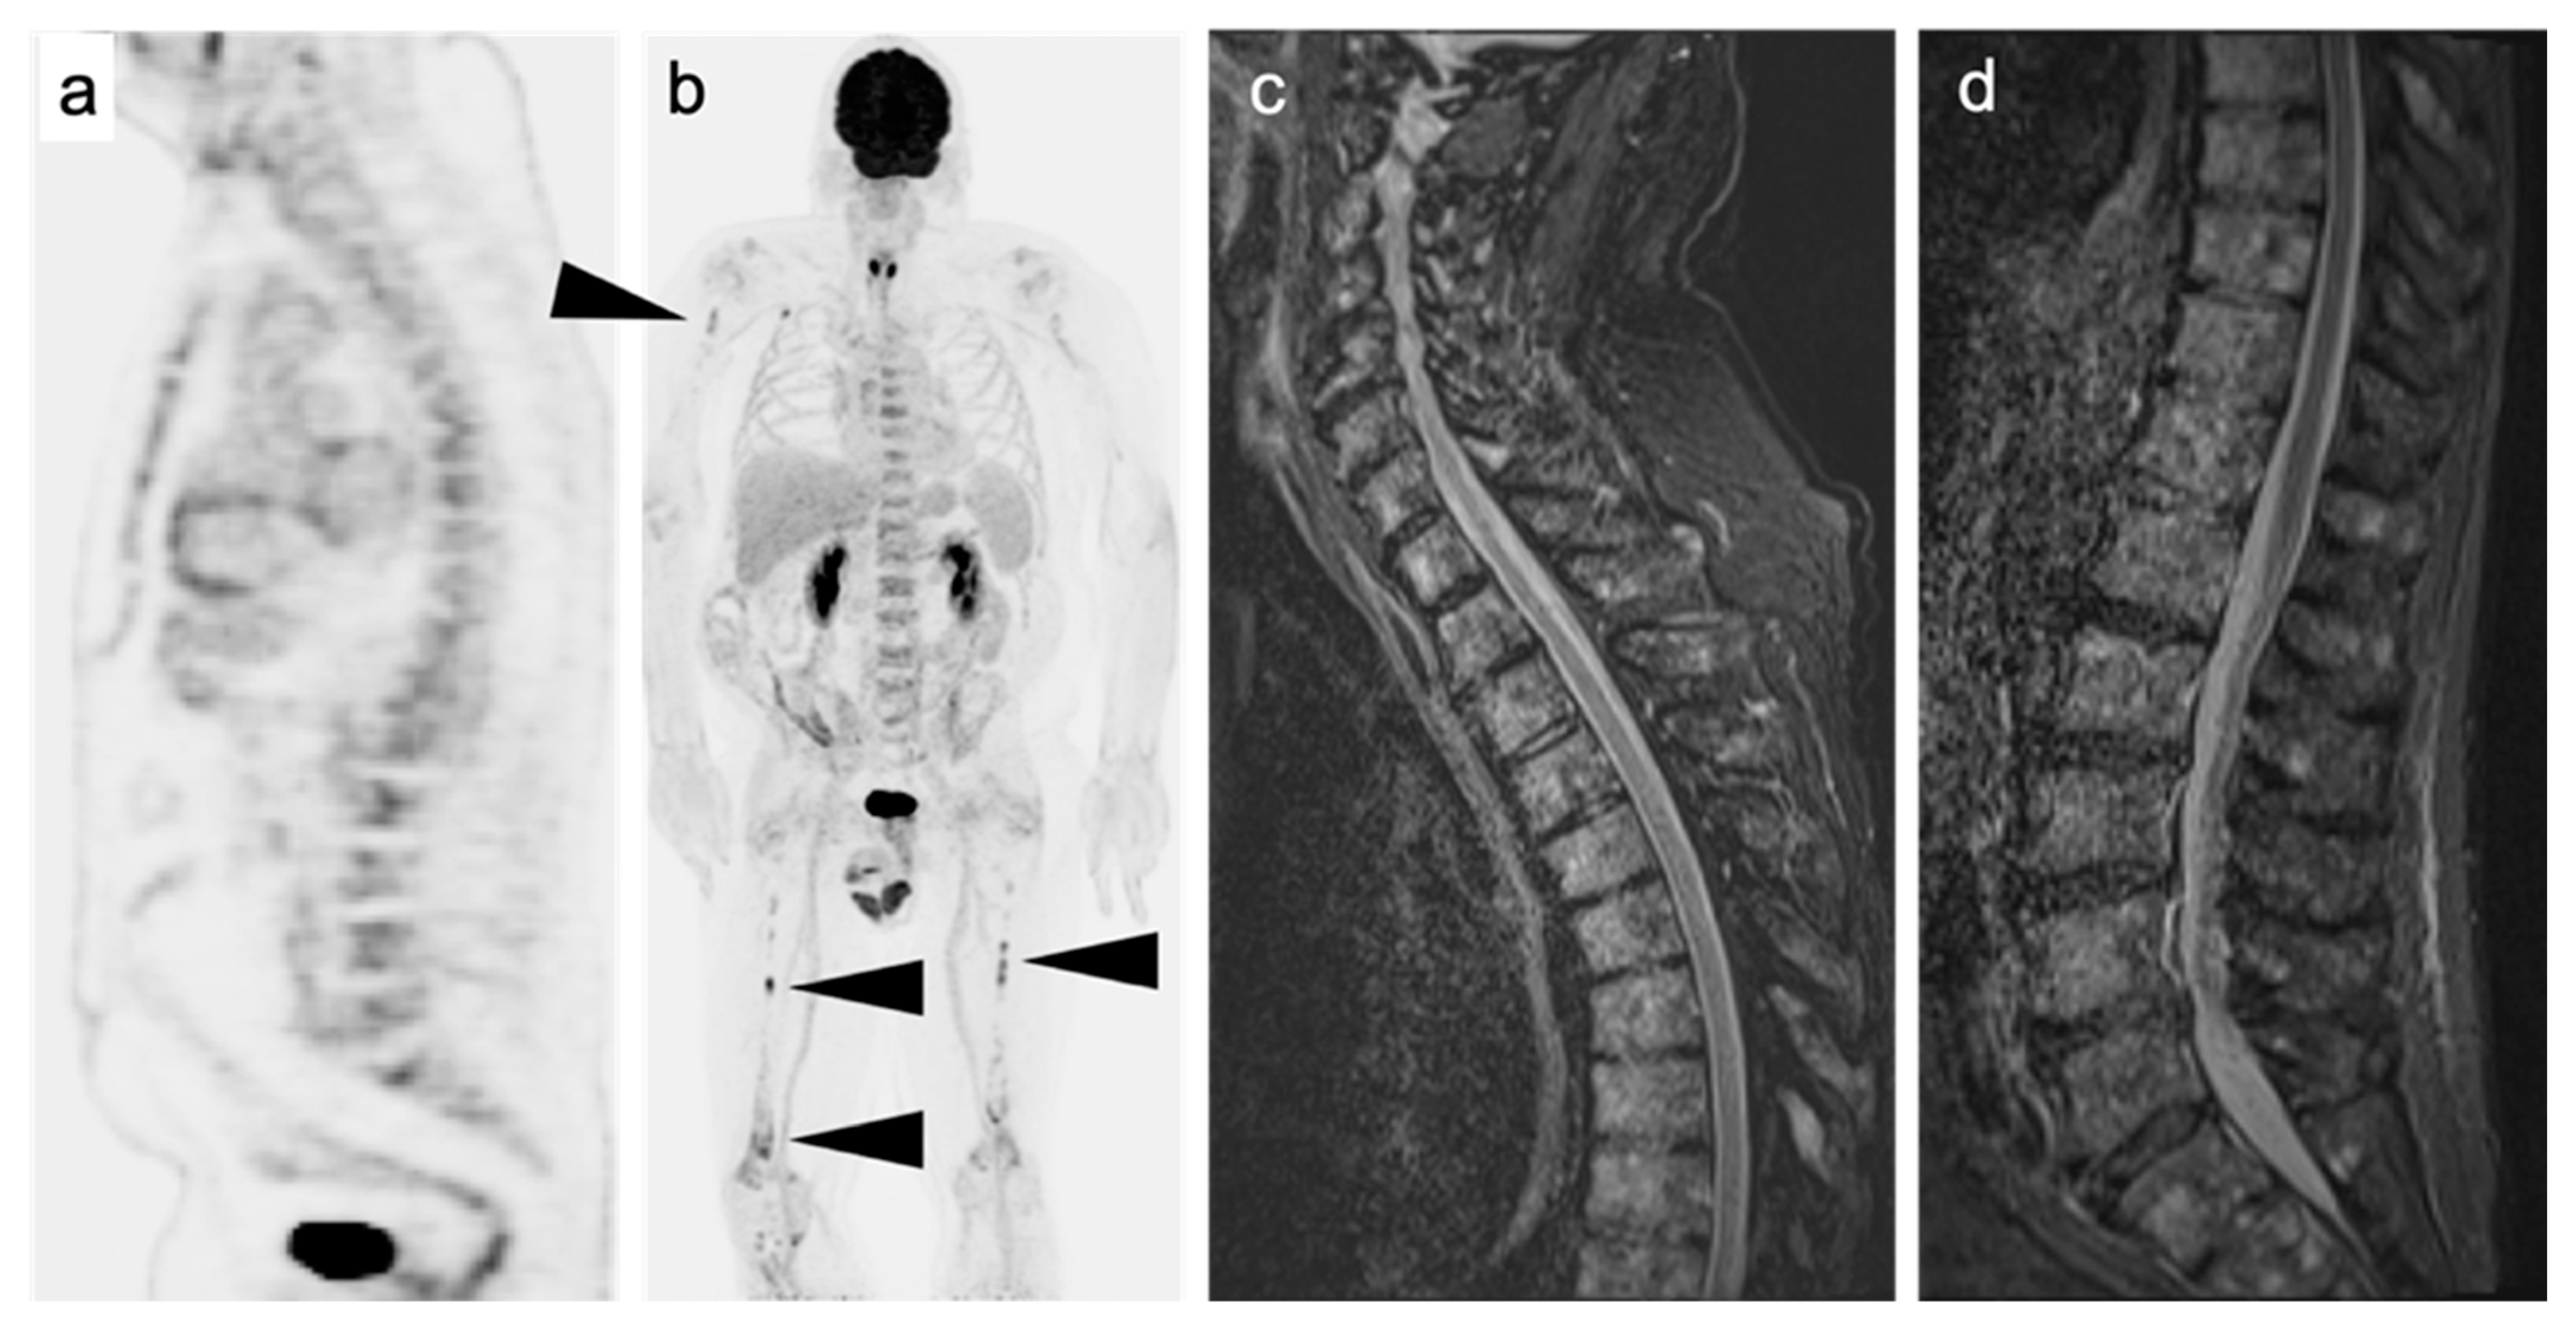

2.3.6. Multiple Myeloma (MM)

- Dimopoulos, M.; Terpos, E.; Comenzo, R.L.; Tosi, P.; Beksac, M.; Sezer, O.; Siegel, D.; Lokhorst, H.; Kumar, S.; Rajkumar, S.V.; et al. International myeloma working group consensus statement and guidelines regarding the current role of imaging techniques in the diagnosis and monitoring of multiple Myeloma. Leukemia 2009, 23, 1545–1556. [Google Scholar] [CrossRef]

- Lütje, S.; de Rooy, J.W.; Croockewit, S.; Koedam, E.; Oyen, W.J.; Raymakers, R.A. Role of radiography, MRI and FDG-PET/CT in diagnosing, staging and therapeutical evaluation of patients with multiple myeloma. Ann. Hematol. 2009, 88, 1161–1168. [Google Scholar] [CrossRef] [PubMed]

- Mayerhoefer, M.E.; Archibald, S.J.; Messiou, C.; Staudenherz, A.; Berzaczy, D.; Schöder, H. MRI and PET/MRI in hematologic malignancies. J. Magn. Reson. Imaging 2020, 51, 1325–1335. [Google Scholar] [CrossRef] [PubMed]

- Yokoyama, K.; Tsuchiya, J.; Tateishi, U. Comparison of [18F]FDG PET/CT and MRI for Treatment Response Assessment in Multiple Myeloma: A Meta-Analysis. Diagnostics 2021, 11, 706. [Google Scholar] [CrossRef] [PubMed]

- Rama, S.; Suh, C.H.; Kim, K.W.; Durieux, J.C.; Ramaiya, N.H.; Tirumani, S.H. Comparative Performance of Whole-Body MRI and FDG PET/CT in Evaluation of Multiple Myeloma Treatment Response: Systematic Review and Meta-Analysis. AJR Am. J. Roentgenol. 2022, 218, 602–613. [Google Scholar] [CrossRef] [PubMed]